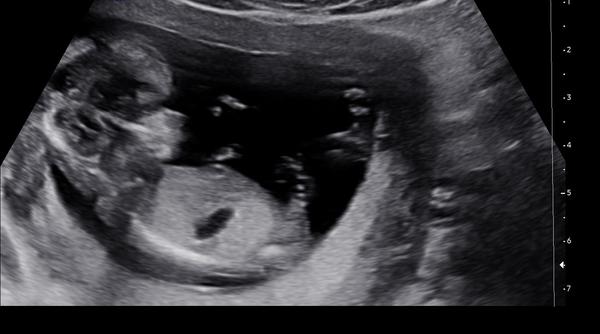

Dokáže lékař odhadnout pohlaví v 13. týdnu?

Ahoj všichni! Doktor mi dnes ve 13. týdnu řekl, že odhaduje kluka. Hodně jsem četla, že v brzkých týdnech je to celkem nerozeznatelné. Dokáže někdo třeba porovnat se svým ultrazvukem? Popř. Trefil se doktor vám?